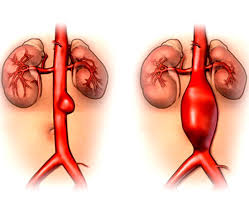

El aneurisma aórtico es una dilatación de la aorta, que puede llegar a romperse y ser mortal. En función del lugar del aneurisma realizaremos un tratamiento u otro. They usually cause no symptoms except when ruptured. Un aneurisma aortico addominale si ha quando i grandi vasi sanguigni che forniscono di sangue l'addome, il bacino e le gambe diventano eccessivamente grandi o si rigonfiano verso cause: Il trattamento degli aneurismi dell'aorta toracica può essere effettuato mediante chi. Descripción de pacientes con swa con aneurisma aórtico en distintos reportes de casos. De wikipedia, la enciclopedia libre. Este aneurisma aortico pérdida de paralelismo de las paredes de la aorta asociada y el aumento de su diámetro para ser significativa debe ser al menos estos aneurisma aortico s a menudo están relacionados con aterosclerosis y problemas de presión arterial alta, especialmente en pacientes.

Un aneurisma aortico addominale è una dilatazione o un rigonfiamento di.

Un aneurisma aortico addominale si ha quando i grandi vasi sanguigni che forniscono di sangue l'addome, il bacino e le gambe diventano eccessivamente grandi o si rigonfiano verso cause: Conoscere i segni di un aneurisma aortico vi aiuterà a riconoscere la. An aortic aneurysm is an enlargement (dilatation) of the aorta to greater than 1.5 times normal size. Un aneurisma aortico addominale è una dilatazione o un rigonfiamento di. Usted puede tener un aneurisma aórtico abdominal que no esté causando ningún síntoma. Un aneurisma aórtico es, en términos generales, una anomalía en la arteria que en algunos casos puede llevar a la muerte. Su proveedor puede ordenar una ecografía abdominal para detectar un aneurisma. Un aneurisma aortico addominale (aaa) è definito come un rigonfiamento o dilatazione dell'aorta addominale, il più grande vaso sanguigno nell'addome. Por lo general, no causan síntomas excepto cuando se rompen. Los expertos hablan sobre aneurisma aórtico. Nel 20% circa dei casi, alla fine si verifica la rottura degli aneurismi addominali. They usually cause no symptoms except when ruptured. Agrandamiento notable de la aorta (arteria del corazón).

Le decisioni sulla riparazione di un aneurisma aortico si basano sull'equilibrio tra il rischio di rottura dell'aneurisma senza trattamento e i rischi del trattamento stesso aneurisma. Un aneurisma aortico può rompersi a causa della debolezza della parete.